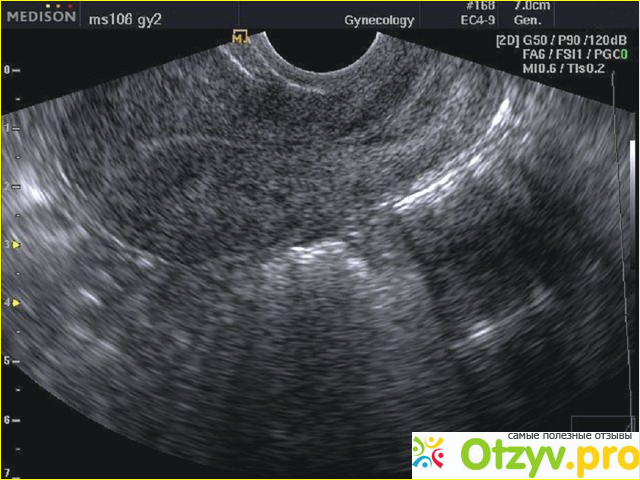

УЗИ матки как метод исследовния

Проведение процедуры обследования

При проведении обследования можно в данном случае получить много полезной и ценной информации, - в частности выявить спаечный процесс, который является результатом протекающего воспаления. Также легко при этом в большинстве случаев выявить пороки, из-за которых становится невозможным зачатие ребенка. При помощи УЗИ также определяется состояние матки, ее форма и как она расположена. Процедуру можно проводить по разным методикам и как она будет проводиться зависит от решения гинеколога – в зависимости от того, что нужно обследовать. Очень популярно применение трансвагинального метода связанного с применением специального датчика, который вводят через влагалище. При этом происходит максимальное приближение к органу, что позволяет получить максимально достоверную информацию. При трансабдоминальном методе исследование провидится через переднюю брюшную стенку. При этом, как было сказано выше, мочевой пузырь должен быть наполнен.